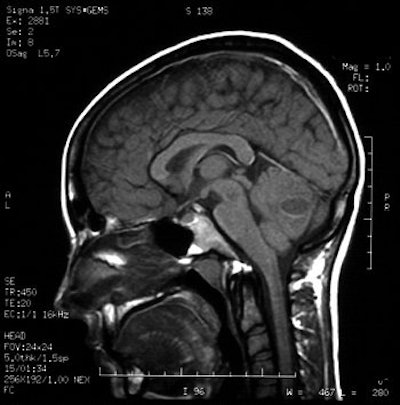

Gadolinium-enhanced MRI scans confirmed the presence of a cerebellar brain abscess in a 22-year-old woman who had undergone tongue piercing four weeks earlier. Images courtesy of Dr Richard Martinello.

However, a brain CT scan revealed a "right cerebellar enhancing lesion with surrounding edema, and an MRI scan with gadolinium confirmed the presence of a solitary brain abscess," the authors reported. The patient underwent a right suboccipital craniotomy to drain the abscess and was then treated with antibiotics. A follow-up CT showed complete resolution of the abscess.